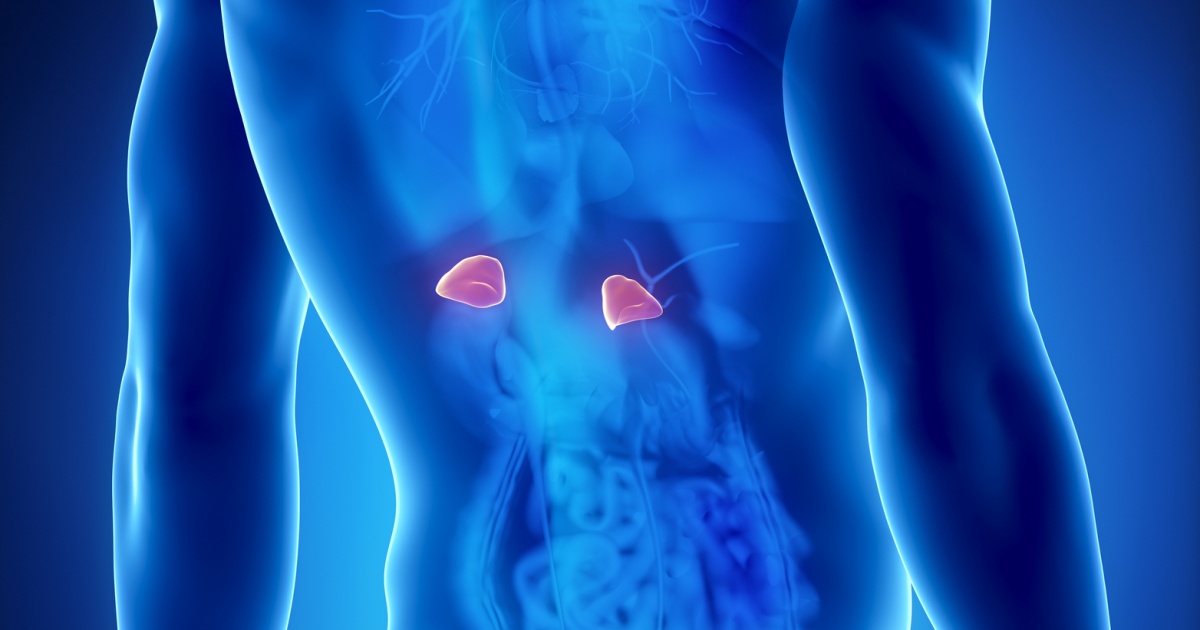

Toto jsou nejčastější příznaky nemocných nadledvin, o kterých 90 % lidí nemá nejmenší zdání

Bolest lokalizovaná v oblasti beder nebo břicha může být další známkou potenciálních potíží s ledvinami. Ledviny se nacházejí v bederní oblasti těla, a pokud jsou postiženy, mohou způsobit nepříjemné bolesti v této oblasti.